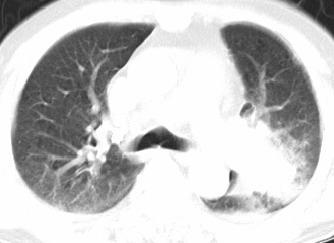

以下是引用xianxianzhongyi在2008-4-20 14:44:00的发言:[br]本人愚见:次病例短短两月的时间,呈现如此大面积实变,病变增长过于迅速,此其一。其二,病变在动脉早期既有明显强化。其三,左上叶后段及下叶背段多叶受累。其四,肺门及纵隔内未见明显肿大的淋巴结。估计层面较厚段支气管显示不清。 诊断:炎性实变可能性大。

以下是引用光影相伴在2008-4-20 14:39:00的发言:[br]支持:1)左侧中央型肺癌伴左肺上叶阻塞性肺炎。、[br] 2)双侧少量胸腔积液。